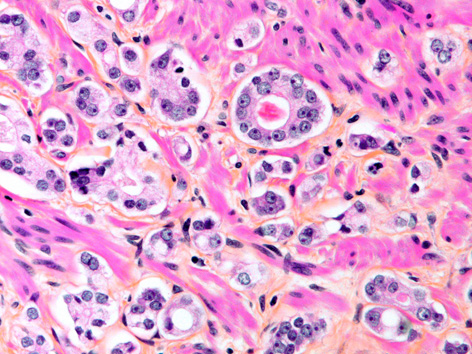

A microscope view of prostate cancer. Photo courtesy of David M. Berman, 2014.

Prostate cancer is the second most commonly diagnosed cancer among Canadian men but only about half of these cancers grow rapidly enough to require treatment.

However, determining which prostate cancers need to be treated can be tricky because it’s hard to predict through biopsy which cancers will eventually become harmful.  In fact, because biopsies often do not yield accurate information, between a third and half of patients initially diagnosed with harmless prostate cancers are likely to be “upgraded” to potentially harmful cancers within a year or two of diagnosis.

A research team led by Dr. David Berman, a professor in the Department of Pathology and Molecular Medicine at Queen’s, and Dr. Tamara Lotan from Johns Hopkins University discovered that the decline of a specific protein within a tumour could help identify the tumours requiring treatment.

“We have shown that a tumour-suppressing protein called phosphatase and tensin homolog, or PTEN, is lost most frequently in prostate tumours that will become harmful and require treatment,” says Dr. Berman. “The team from Johns Hopkins has done a terrific job of making this test more reliable and valid and applicable to prostate cancer and to other forms of cancer.”

Currently, the Gleason Grading system is used to determine the harmful potential of prostate cancers. Scores usually range from 6 to 10, with lower numbers often indicating cancers that are unlikely to become harmful.

One hundred and seventy four prostate cancer patients with a Gleason score of 6 had The team measured PTEN levels in cancers biopsied from 174 patients, who appeared to have harmless cancers with Gleason scores of 6 or less.   Seventy-one of these cases were upgraded to potentially harmful cancers with a score of 7 after the entire prostate was surgically removed and examined by pathologists. Importantly, PTEN loss found in biopsies helped separate harmless cancers from their more dangerous look-alikes.

“The 71 patients who had their tumours upgraded had a three times higher rate of PTEN loss than the group that was accurately graded,” says Dr. Berman. “Although the percentage of patients who have PTEN loss is low, this finding is extremely exciting as it proves that measuring proteins in biopsies can improve accuracy.  Also, it’s a fairly simple test that could be done in any pathology lab.”